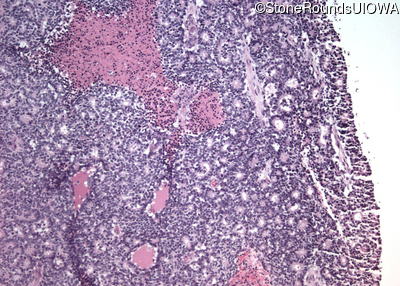

Pathology - Left - -

Exemplar